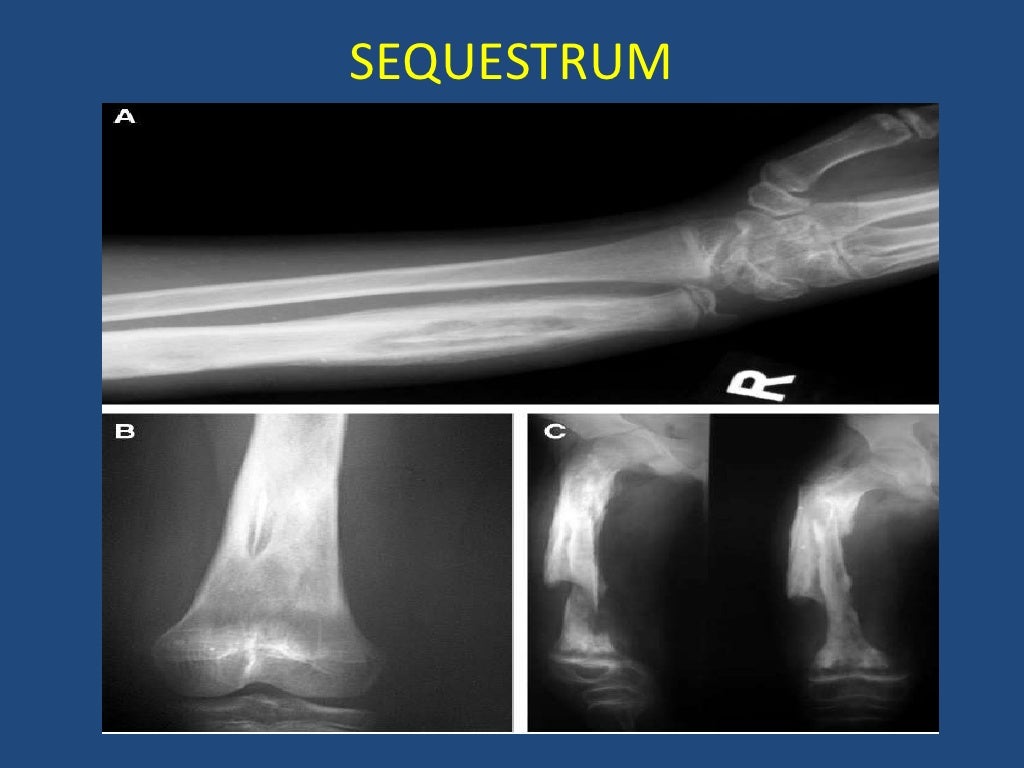

From www.slideshare.net

Chronic Osteomyelitis In Children Osteomyelitis Symptoms In Toddlers Swelling, warmth and redness over the area of the infection; Have swelling, redness, warmth or pain in the area. Not want to use the affected. It's usually caused by a bacterial infection. Acute osteomyelitis (ao) and acute septic arthritis (sa) should be considered in all children who present with pain involving a bone. What are the symptoms of osteomyelitis? Signs. Osteomyelitis Symptoms In Toddlers.

Chronic Osteomyelitis In Children Osteomyelitis Symptoms In Toddlers The following are the most common symptoms of osteomyelitis. Signs and symptoms of osteomyelitis include: What are the symptoms of osteomyelitis? Call us to schedule 513. Not want to use the affected. Osteomyelitis is the medical term for inflammation in a bone. Acute osteomyelitis (ao) and acute septic arthritis (sa) should be considered in all children who present with pain. Osteomyelitis Symptoms In Toddlers.

Chronic Osteomyelitis In Children Osteomyelitis Symptoms In Toddlers Not want to use the affected. The following are the most common symptoms of osteomyelitis. It's usually caused by a bacterial infection. Signs and symptoms of osteomyelitis. Call us to schedule 513. Have swelling, redness, warmth or pain in the area. Osteomyelitis is the medical term for inflammation in a bone. Acute osteomyelitis (ao) and acute septic arthritis (sa) should. Osteomyelitis Symptoms In Toddlers.

Chronic Osteomyelitis In Children Osteomyelitis Symptoms In Toddlers Acute osteomyelitis (ao) and acute septic arthritis (sa) should be considered in all children who present with pain involving a bone. Signs and symptoms of osteomyelitis. Have swelling, redness, warmth or pain in the area. The following are the most common symptoms of osteomyelitis. Swelling, warmth and redness over the area of the infection; What are the symptoms of osteomyelitis?. Osteomyelitis Symptoms In Toddlers.

Chronic Osteomyelitis In Children Osteomyelitis Symptoms In Toddlers Not want to use the affected. Signs and symptoms of osteomyelitis include: Call us to schedule 513. Swelling, warmth and redness over the area of the infection; It's usually caused by a bacterial infection. Osteomyelitis is the medical term for inflammation in a bone. Signs and symptoms of osteomyelitis. The following are the most common symptoms of osteomyelitis. What are. Osteomyelitis Symptoms In Toddlers.